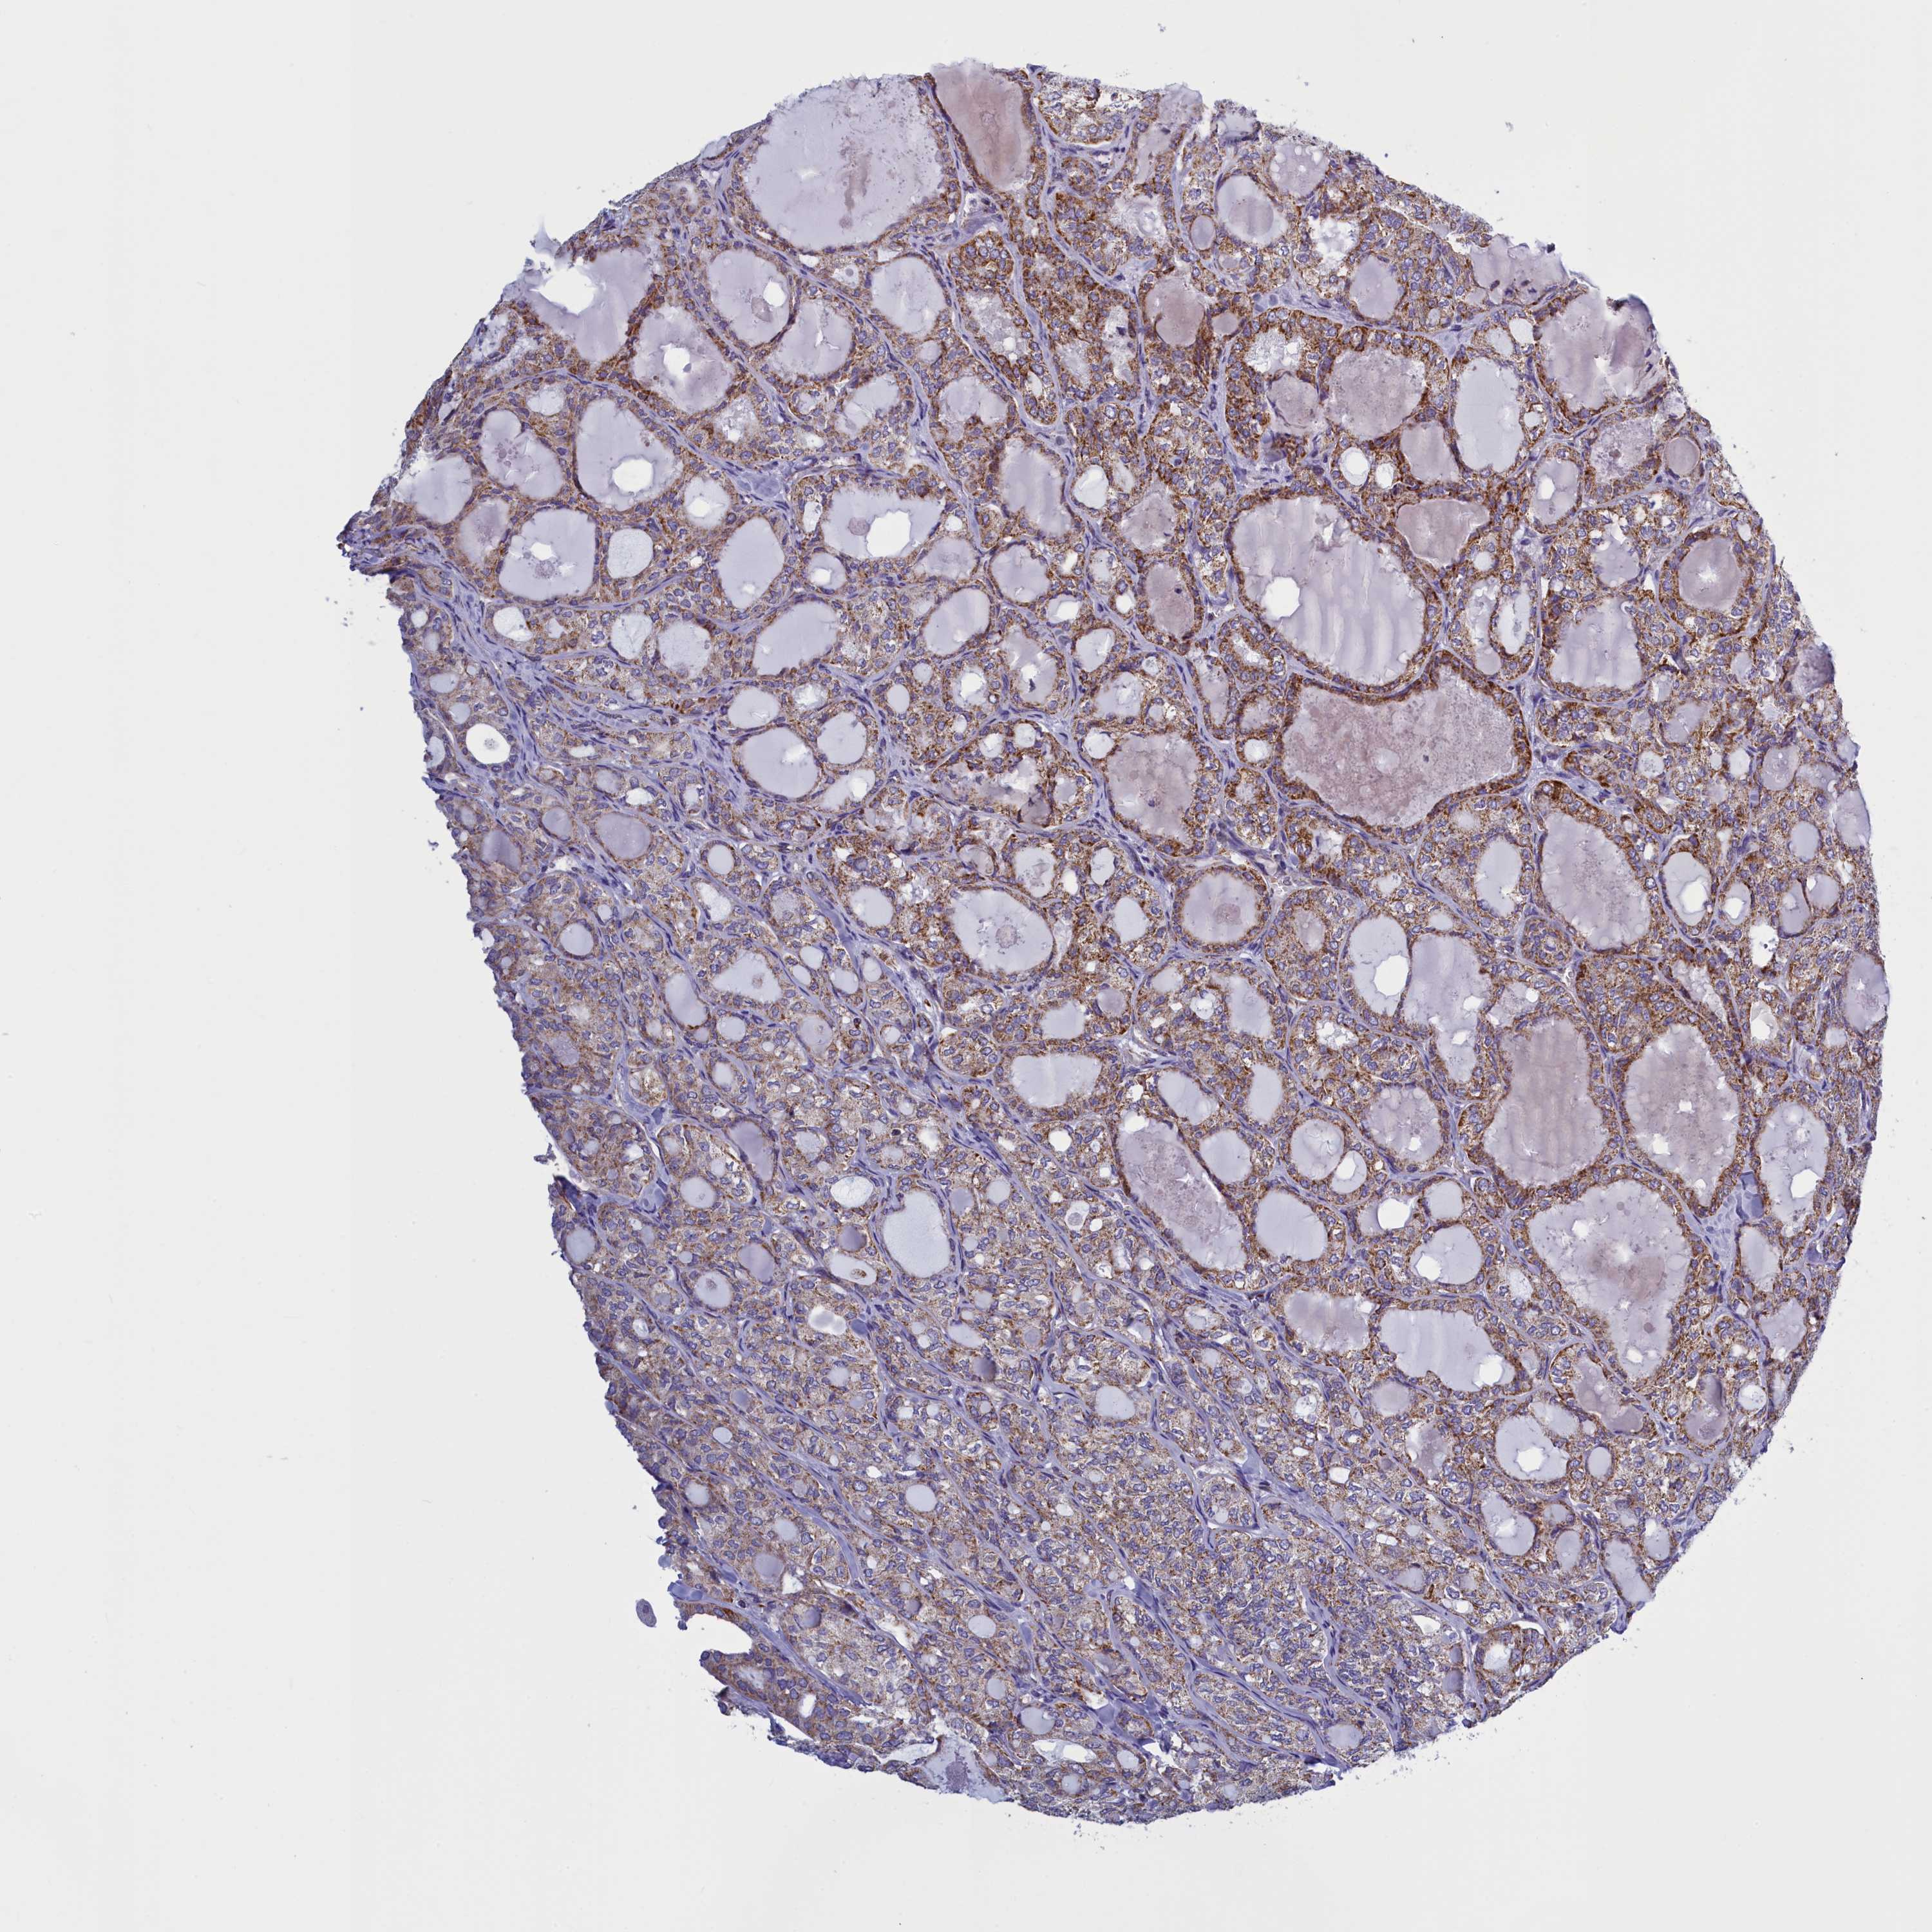

THYROID CANCER - Protein expressioni

A mouse-over function shows sample information and annotation data. Click on an image to view it in a full screen mode. Samples can be filtered based on level of antibody staining by selecting one or several of the following categories: high, medium, low and not detected. The assay and annotation is described here.

Note that samples used for immunohistochemistry by the Human Protein Atlas do not correspond to samples in the TCGA dataset.

Antibody stainingi

Antibody staining in the annotated cell types in the current human tissue is reported as not detected, low, medium, or high, based on conventional immunohistochemistry profiling in selected tissues. This score is based on the combination of the staining intensity and fraction of stained cells.

Each image is clickable and will lead to virtual microscopy that enables deeper exploration of all samples and also displays staining intensity scores, fraction scores and subcellular localization as well as patient and tissue information for each sample.

Antibody HPA041815

Staining

High

Medium

Low

Not detected

Intensity

Strong

Moderate

Weak

Negative

Quantity

>75%

75%-25%

<25%

None

Location

Nuclear

Cytoplasmic/membranous

Cytoplasmic/membranous,nuclear

Papillary adenocarcinoma, NOS

Follicular adenoma carcinoma, NOS